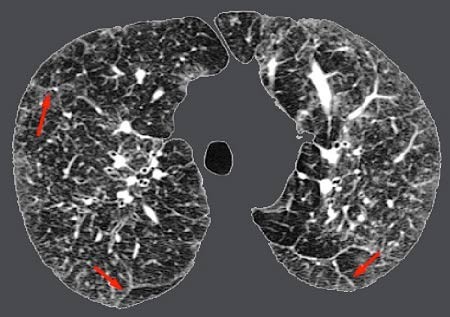

Chụp cắt lớp vi tính: Đây là phương pháp có thể phát hiện ra bệnh kẽ phổi vì nó cung cấp hình ảnh về cấu trúc toàn diện của phổi.